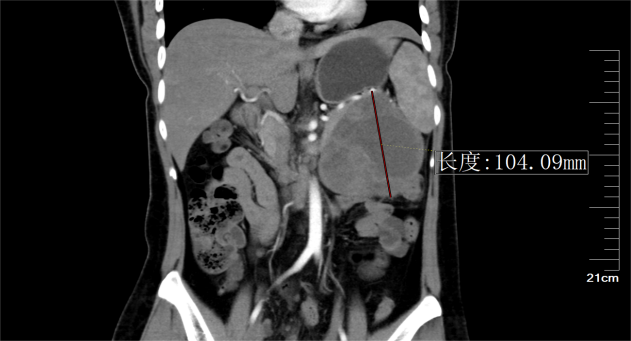

古主任接诊后,为甘女士进行了细致的检查后,结合影像学检查结果分析,考虑患者胰腺体尾部占位为胰腺实性-假乳头状瘤可能,肿瘤巨大,压迫周围脏器组织,侵犯包绕脾动静脉,需行外科手术切除治疗。

▶ 胰体尾部囊实性巨大占位的CT影像

古主任介绍此次3D腹腔镜下胰体尾联合脾脏切除术有两大大挑战。一是风险高,病灶位于胰体尾,挤压到左肾、胃、脾等器官,侵犯包绕脾动静脉,其周围集中了腹腔重要的血管、器官,术中分离困难,出血风险大,损伤任何一个组织都可能导致术后出现严重并发症。二是操作空间小,由于患者病灶为胰腺体尾部囊实性巨大占位,最大直径超过10cm,病灶基本充满左上腹,行微创操作,手术视野的暴露及操作的空间很小,对术者手术操作技巧要求更高。